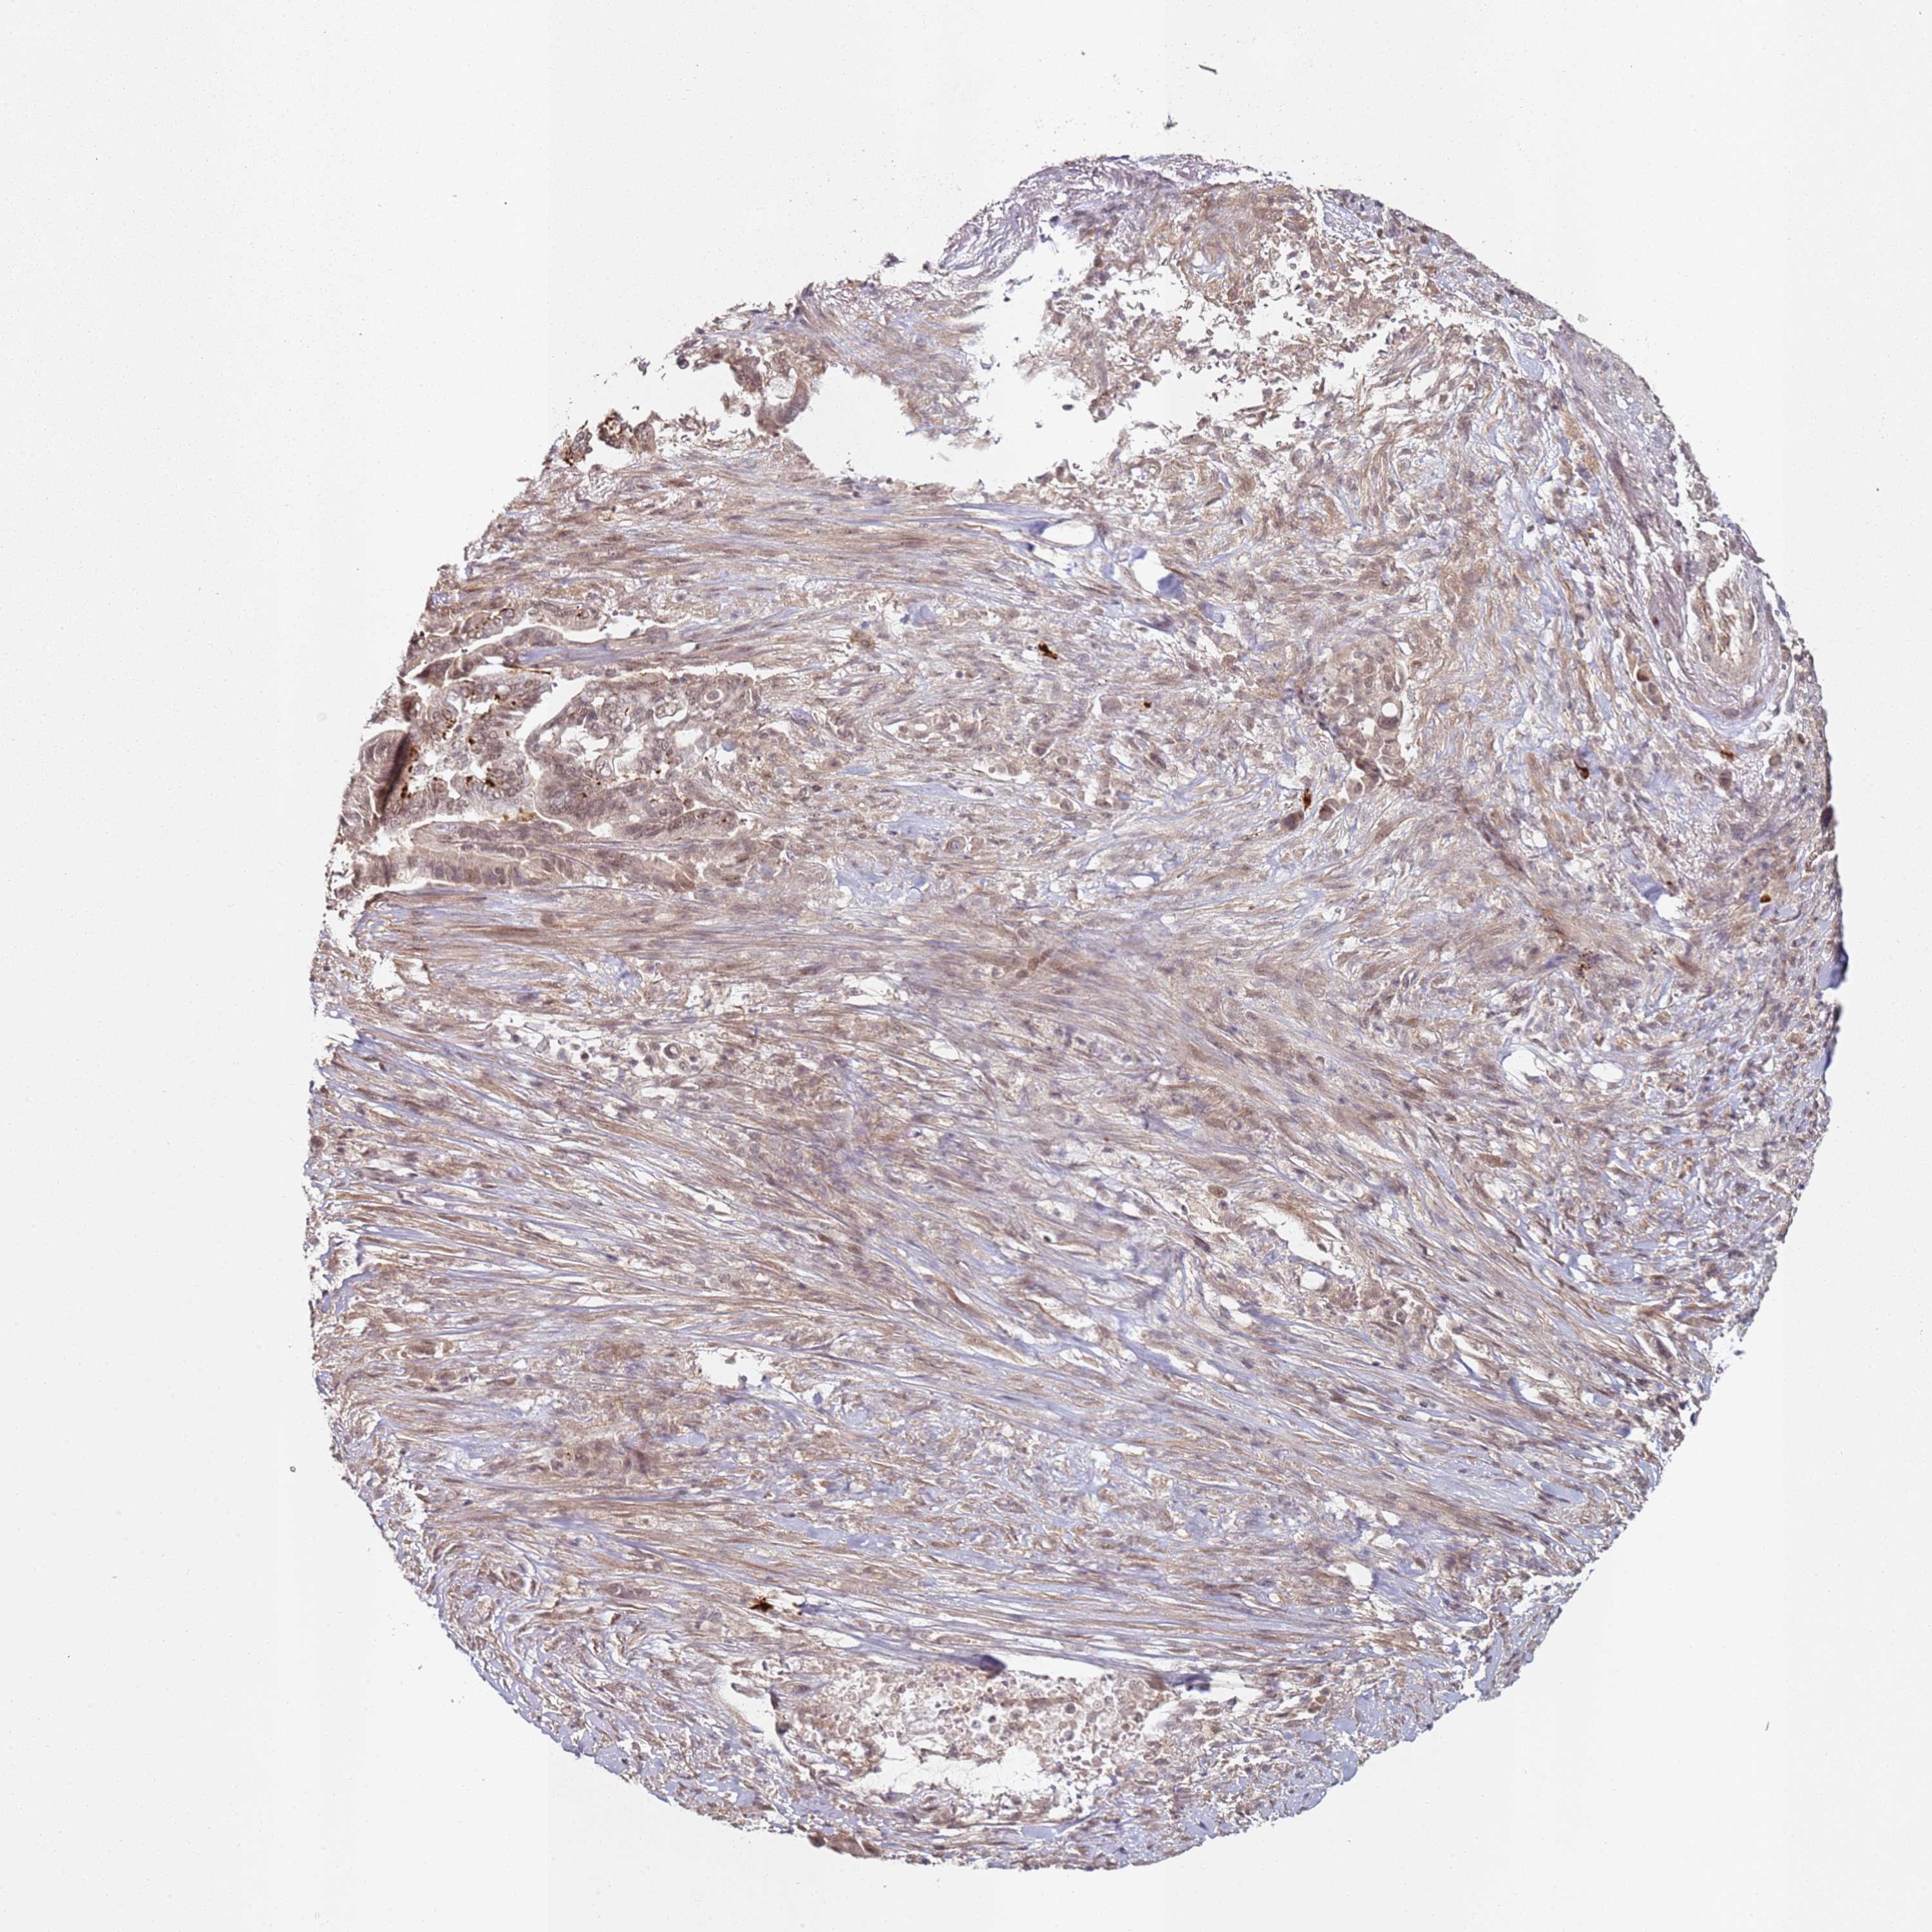

PANCREATIC CANCER - Protein expressioni

A mouse-over function shows sample information and annotation data. Click on an image to view it in a full screen mode. Samples can be filtered based on level of antibody staining by selecting one or several of the following categories: high, medium, low and not detected. The assay and annotation is described here.

Note that samples used for immunohistochemistry by the Human Protein Atlas do not correspond to samples in the TCGA dataset.

Antibody stainingi

Antibody staining in the annotated cell types in the current human tissue is reported as not detected, low, medium, or high, based on conventional immunohistochemistry profiling in selected tissues. This score is based on the combination of the staining intensity and fraction of stained cells.

Each image is clickable and will lead to virtual microscopy that enables deeper exploration of all samples and also displays staining intensity scores, fraction scores and subcellular localization as well as patient and tissue information for each sample.

Antibody HPA046871

Staining

High

Medium

Low

Not detected

Intensity

Strong

Moderate

Weak

Negative

Quantity

>75%

75%-25%

<25%

None

Location

Nuclear

Cytoplasmic/membranous

Cytoplasmic/membranous,nuclear

Adenocarcinoma, NOS